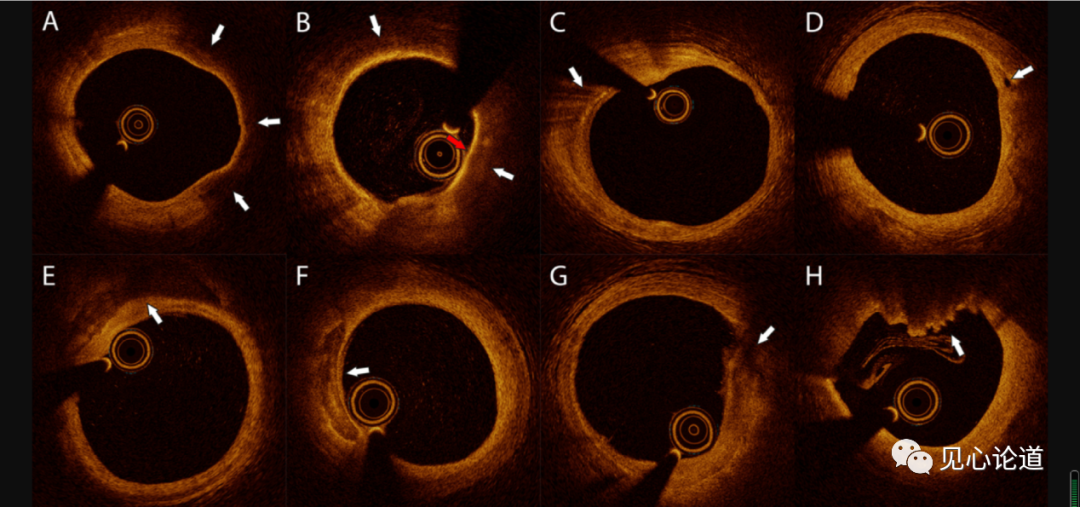

图4: BVS植入后5年新动脉粥样硬化OCT表现

A. 脂质内膜(白色箭头);B.TCFA -脂质新生内膜(白色箭头),薄纤维帽(60um)(红色箭头);C.巨噬细胞浸润(白色箭头);D.新生内膜血管(白色箭头);E.钙化(从端面到管腔边界200um)(白色箭头);F.钙化(距离管腔末端-管腔边缘200um)(白色箭头);G.内膜破裂(白色箭头所指);H.支架外段血栓(白色箭头)。